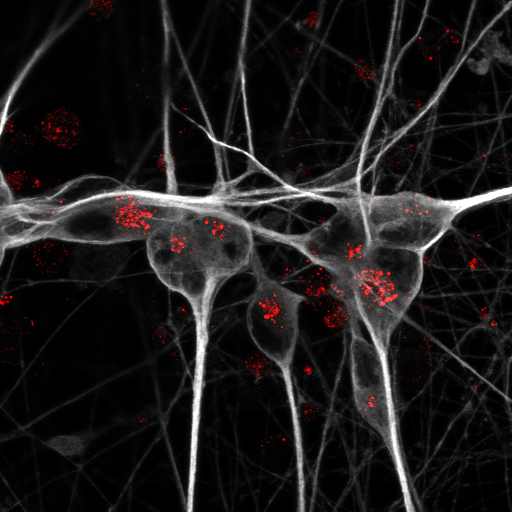

Abbildung: Menschliche Nervenzellen, die aus induzierten pluripotenten Stammzellen gewonnen wurden (grau): Um den ApoE-Rezeptor Sortilin nachzuweisen, haben die Forschenden ihn rot angefärbt.   © Anna K. Greda, Aarhus University

Um zu verstehen, warum die ApoE4-Variante das Risiko für Alzheimer im Vergleich zu ApoE3 so dramatisch erhöht, haben die beiden Erstautorinnen der Studie, Dr. Anna Greda, Assistenzprofessorin in Willnows Arbeitsgruppe in Aarhus, und Dr. Jemila Gomes, die dort promoviert hat und nun als Postdoc in Willnows Berliner Team forscht, mit den Technologieplattformen „Pluripotent Stem Cells“ und „Electron Microscopy“ des Max Delbrück Center zusammengearbeitet. Die Forschenden verwendeten gentechnisch veränderte Mäuse, die das menschliche ApoE3- oder ApoE4-Gen trugen. In ihrem Mausmodell fanden sie heraus, dass das Protein ApoE3 mit einem Rezeptor namens Sortilin interagiert, um Fettsäuren in die Nervenzellen zu transportieren. ApoE4 hingegen stört die Funktion von Sortilin und verhindert so die Aufnahme der Lipide in die Neuronen.

Im nächsten Schritt prüften die Wissenschaftler*innen, ob ihre an Mäusen gewonnenen Erkenntnisse auch für die Gesundheit des menschlichen Gehirns relevant sind. Sie nutzten dafür Neuronen und Astrozyten mit verschiedenen ApoE-Genvarianten, die sie aus menschlichen Stammzellen gezüchtet hatten. In den gezüchteten Zellen konnte das Team erneut beobachten, dass ApoE3 es den Neuronen ermöglichte, langkettige Fettsäuren zu verstoffwechseln – während ApoE4 diese Fähigkeit unterband.